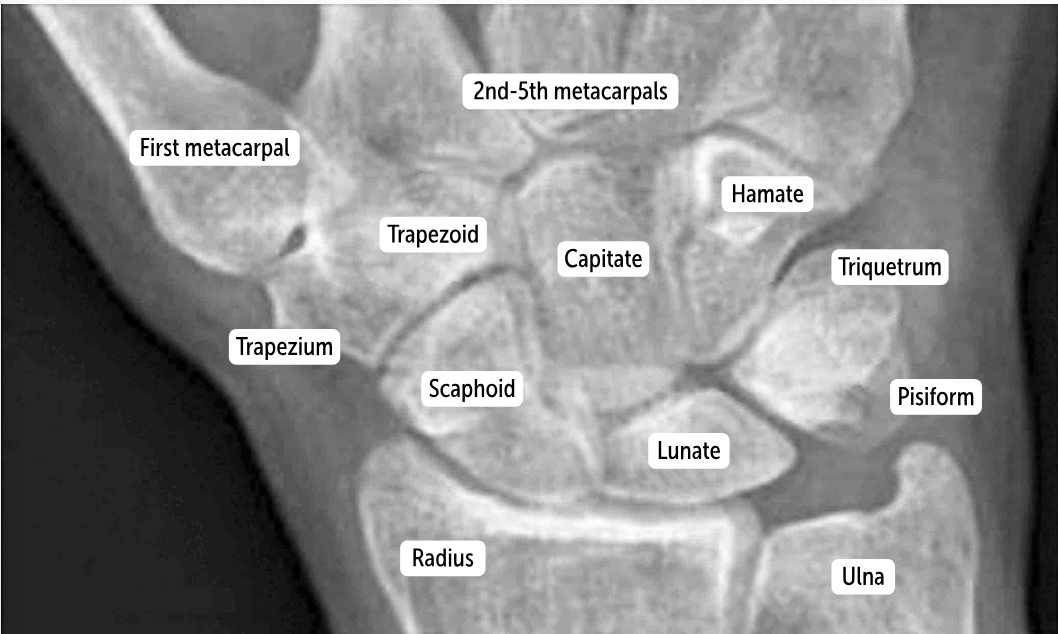

The most commonly fractured carpal bone by falling on an outstretched hand, which has a risk of avascular necrosis, is the __________.

Scaphoid bone

The most commonly dislocated bone after a fall on an outstretched hand is the ___________.

Lunate bone

Carpal bones by row:

So Long To Pinky, Here Comes The Thumb

Scaphoid, Lunate, Triquetrum, Pisiform, Hamate, Capitate, Trapezoid, Trapezium

Scaphoid

Lunate

Triquetrum

Pisiform

Hamate

Capitate

Trapezoid

Trapezium

The two distinct rows articulate with each other at the __________. It’s a plane (simple sliding) joint that acts to amplify all the other wrist actions.

midcarpal joint

Which carpal bones articulate with the metacarpal bones?

The bones of the distal row (hamate, capitate, trapezoid, and trapezium) articulate with the metacarpal bones.